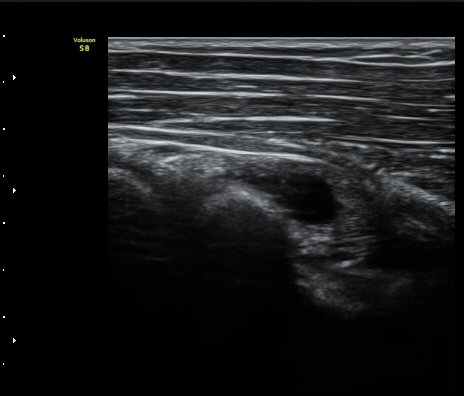

ŽÃËÀÚ¸¦ Á» ´õ ¸»´ÜÀ¸·Î À̵¿ÇÏ´Ï ³¶Á¾Àº ´õ Å©°Ô °üÂûµÈ´Ù(±×¸² 3, 4).